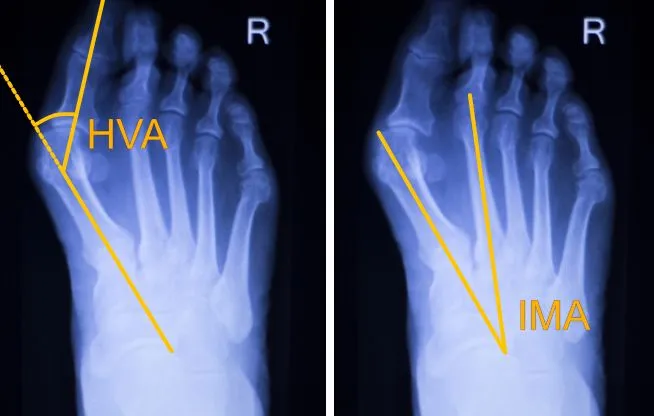

Kluczowym elementem diagnostyki haluksów jest badanie obrazowe, a w szczególności zdjęcie rentgenowskie (RTG) stopy w obciążeniu, czyli wykonane w pozycji stojącej. To niezwykle ważne, ponieważ pozwala ono ocenić strukturę kostną stopy pod wpływem naturalnego obciążenia, co jest niemożliwe w pozycji leżącej. Na podstawie RTG ortopeda może precyzyjnie zmierzyć kąty deformacji, ocenić stopień zaawansowania zmian zwyrodnieniowych w stawie oraz zidentyfikować inne patologie. Te informacje są niezbędne do postawienia dokładnej diagnozy i zaplanowania odpowiedniego, zindywidualizowanego leczenia. Czasem, w bardziej skomplikowanych przypadkach, lekarz może zlecić dodatkowe badania, takie jak rezonans magnetyczny (MRI) czy tomografia komputerowa (CT), aby uzyskać jeszcze bardziej szczegółowy obraz tkanek miękkich lub struktur kostnych.